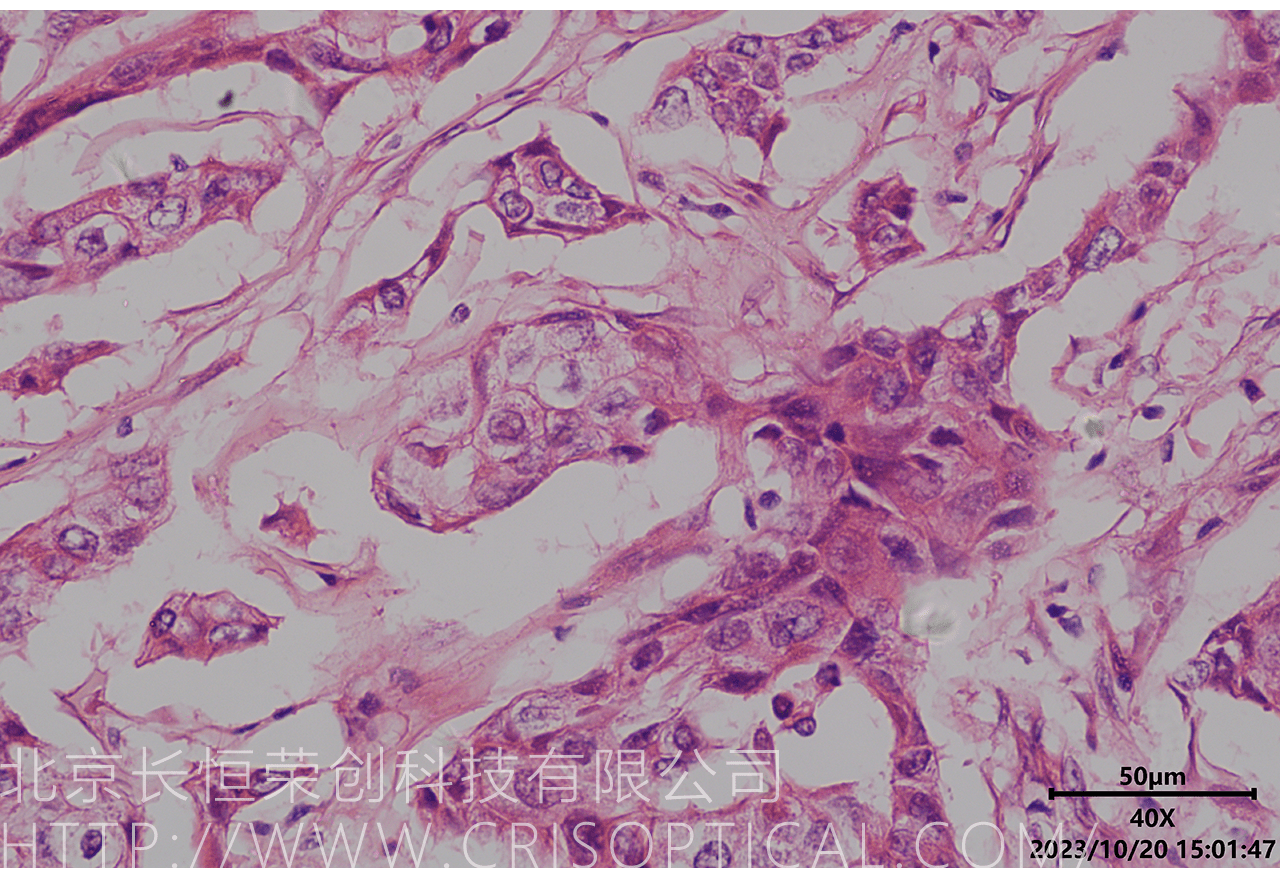

病理切片觀察是一種重要的醫(yī)學(xué)實(shí)踐,通過對(duì)組織和細(xì)胞切片的

顯微鏡觀察,幫助醫(yī)生診斷疾病、評(píng)估病情和制定治療方案。病理切片觀察在

臨床醫(yī)學(xué)、癌癥診斷、外科手術(shù)和疾病研究中發(fā)揮著關(guān)鍵作用。

腫瘤診斷:對(duì)癌癥和其他腫瘤的病理切片觀察是確定腫瘤類型、分級(jí)和分期的關(guān)鍵步驟。醫(yī)生通過觀察組織樣本中的細(xì)胞形態(tài)、核形狀、分裂活性和其他特征,可以識(shí)別腫瘤的類型,幫助決定治療方法。